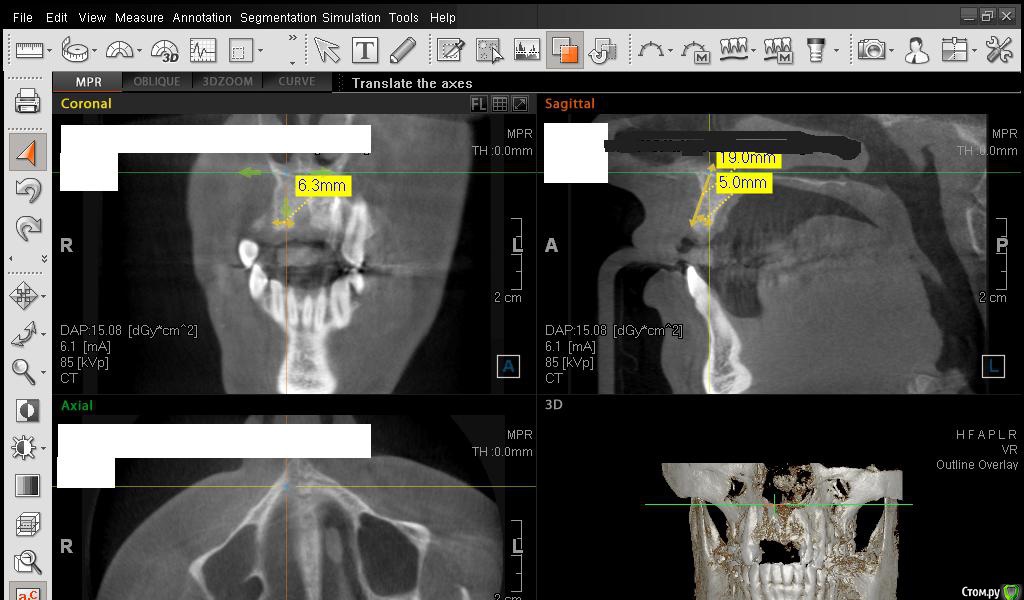

Сестричка Опубликовано 2 марта, 2015 Автор Поделиться Опубликовано 2 марта, 2015 Еще пара срезов Ссылка на комментарий

SDC Опубликовано 2 марта, 2015 Поделиться Опубликовано 2 марта, 2015 Интересны размеры беззубого альвеолярного отростка на самой вершине его или рядом с вершиной на расстоянии 1 мм. от нее в проекции будущего местоположения имплантатов.Желательно размеры проводить рядом с объектом (как в черчении)По-моему, диаметр 3 мм. подходит для имплантации без костной пластики, но без трансплантации десны, одномоментно с имплантацией, не обойтись. 1 Ссылка на комментарий

АнтонТЛТ Опубликовано 2 марта, 2015 Поделиться Опубликовано 2 марта, 2015 Сам крест еще нужно повернуть, чтобы было одна полоса креста была параллельна краю челюсти Ссылка на комментарий

Сестричка Опубликовано 2 марта, 2015 Автор Поделиться Опубликовано 2 марта, 2015 Интересны размеры беззубого альвеолярного отростка на самой вершине его или рядом с вершиной на расстоянии 1 мм. от нее в проекции будущего местоположения имплантатов.Желательно размеры проводить рядом с объектом (как в черчении)По-моему, диаметр 3 мм. подходит для имплантации без костной пластики, но без трансплантации десны, одномоментно с имплантацией, не обойтись.Простите безграмотную, совсем не понимаю что это за отросток и где он находится(( А размеры программа автоматически куда-то уводит, я их хотела поставить как надо, не получается. Про десну понятно, что надо все сразу делать, хирург говорил, у меня дефецит десны и келлоидные шрамы от резекций. Поэтому и предлагал материал для увеличения объема десны, но я конечно тоже больше хотела бы, чтоб взяли с неба. Ссылка на комментарий